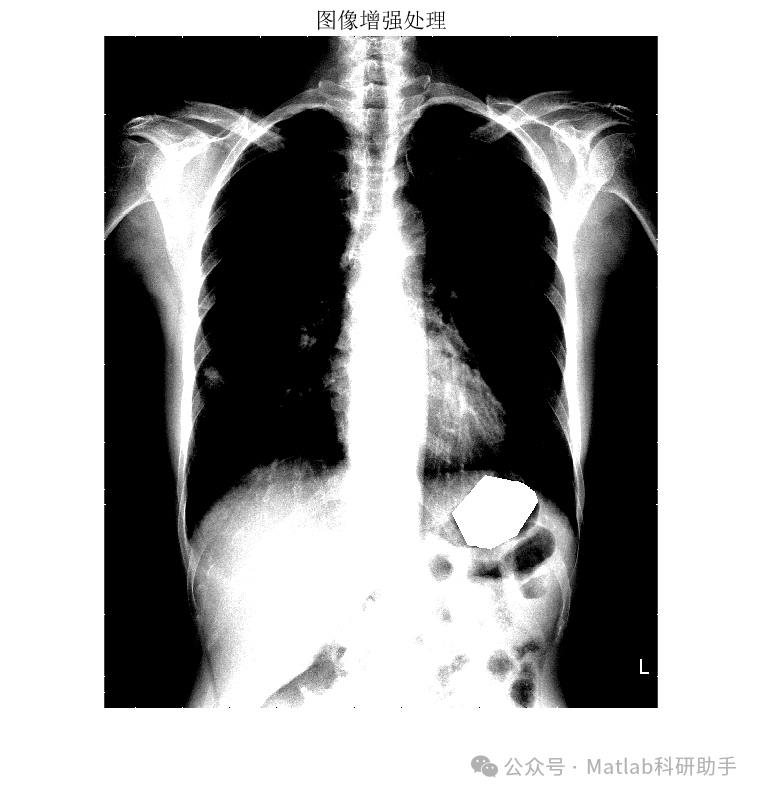

⛳️ 运行结果